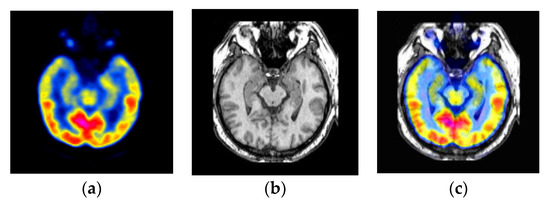

4.1. Medical Diagnosis Applications

- Liu, Y.; Chen, X.; Cheng, J.; Peng, H. A medical image fusion method based on convolutional neural networks. In Proceedings of the 2017 20th International Conference on Information Fusion (Fusion), Xi’an, China, 10–13 July 2017; pp. 1–7. [Google Scholar]

- Kogan, F.; Fan, A.P.; Gold, G.E. Potential of PET-MRI for imaging of non-oncologic musculoskeletal disease. Quant. Imaging Med. Surg. 2016, 6, 756. [Google Scholar] [CrossRef] [PubMed]